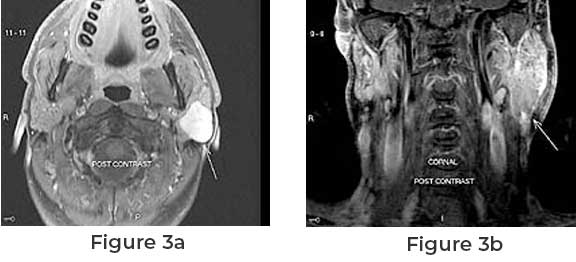

Facial Swelling or Mass

As the tumor grows, it may cause swelling or a palpable mass in the affected area, typically near the ear or along the course of the facial nerve.